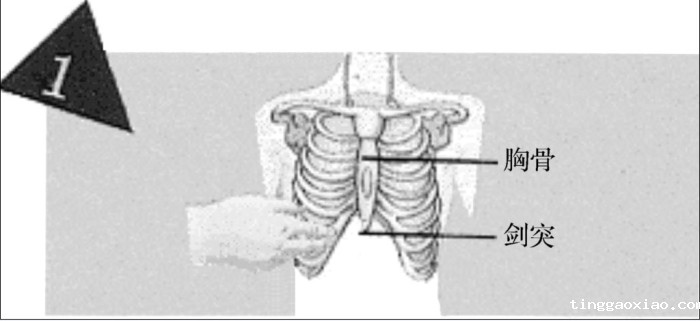

正确的胸外按压位置:

由病人的胸部(近施救者侧),找寻肋骨下缘,沿肋骨缘向上滑动,至肋骨与胸骨交汇的胸窝处,即为按压位置。

将中指置于心窝处,食指紧靠中指,置于胸骨上定位。